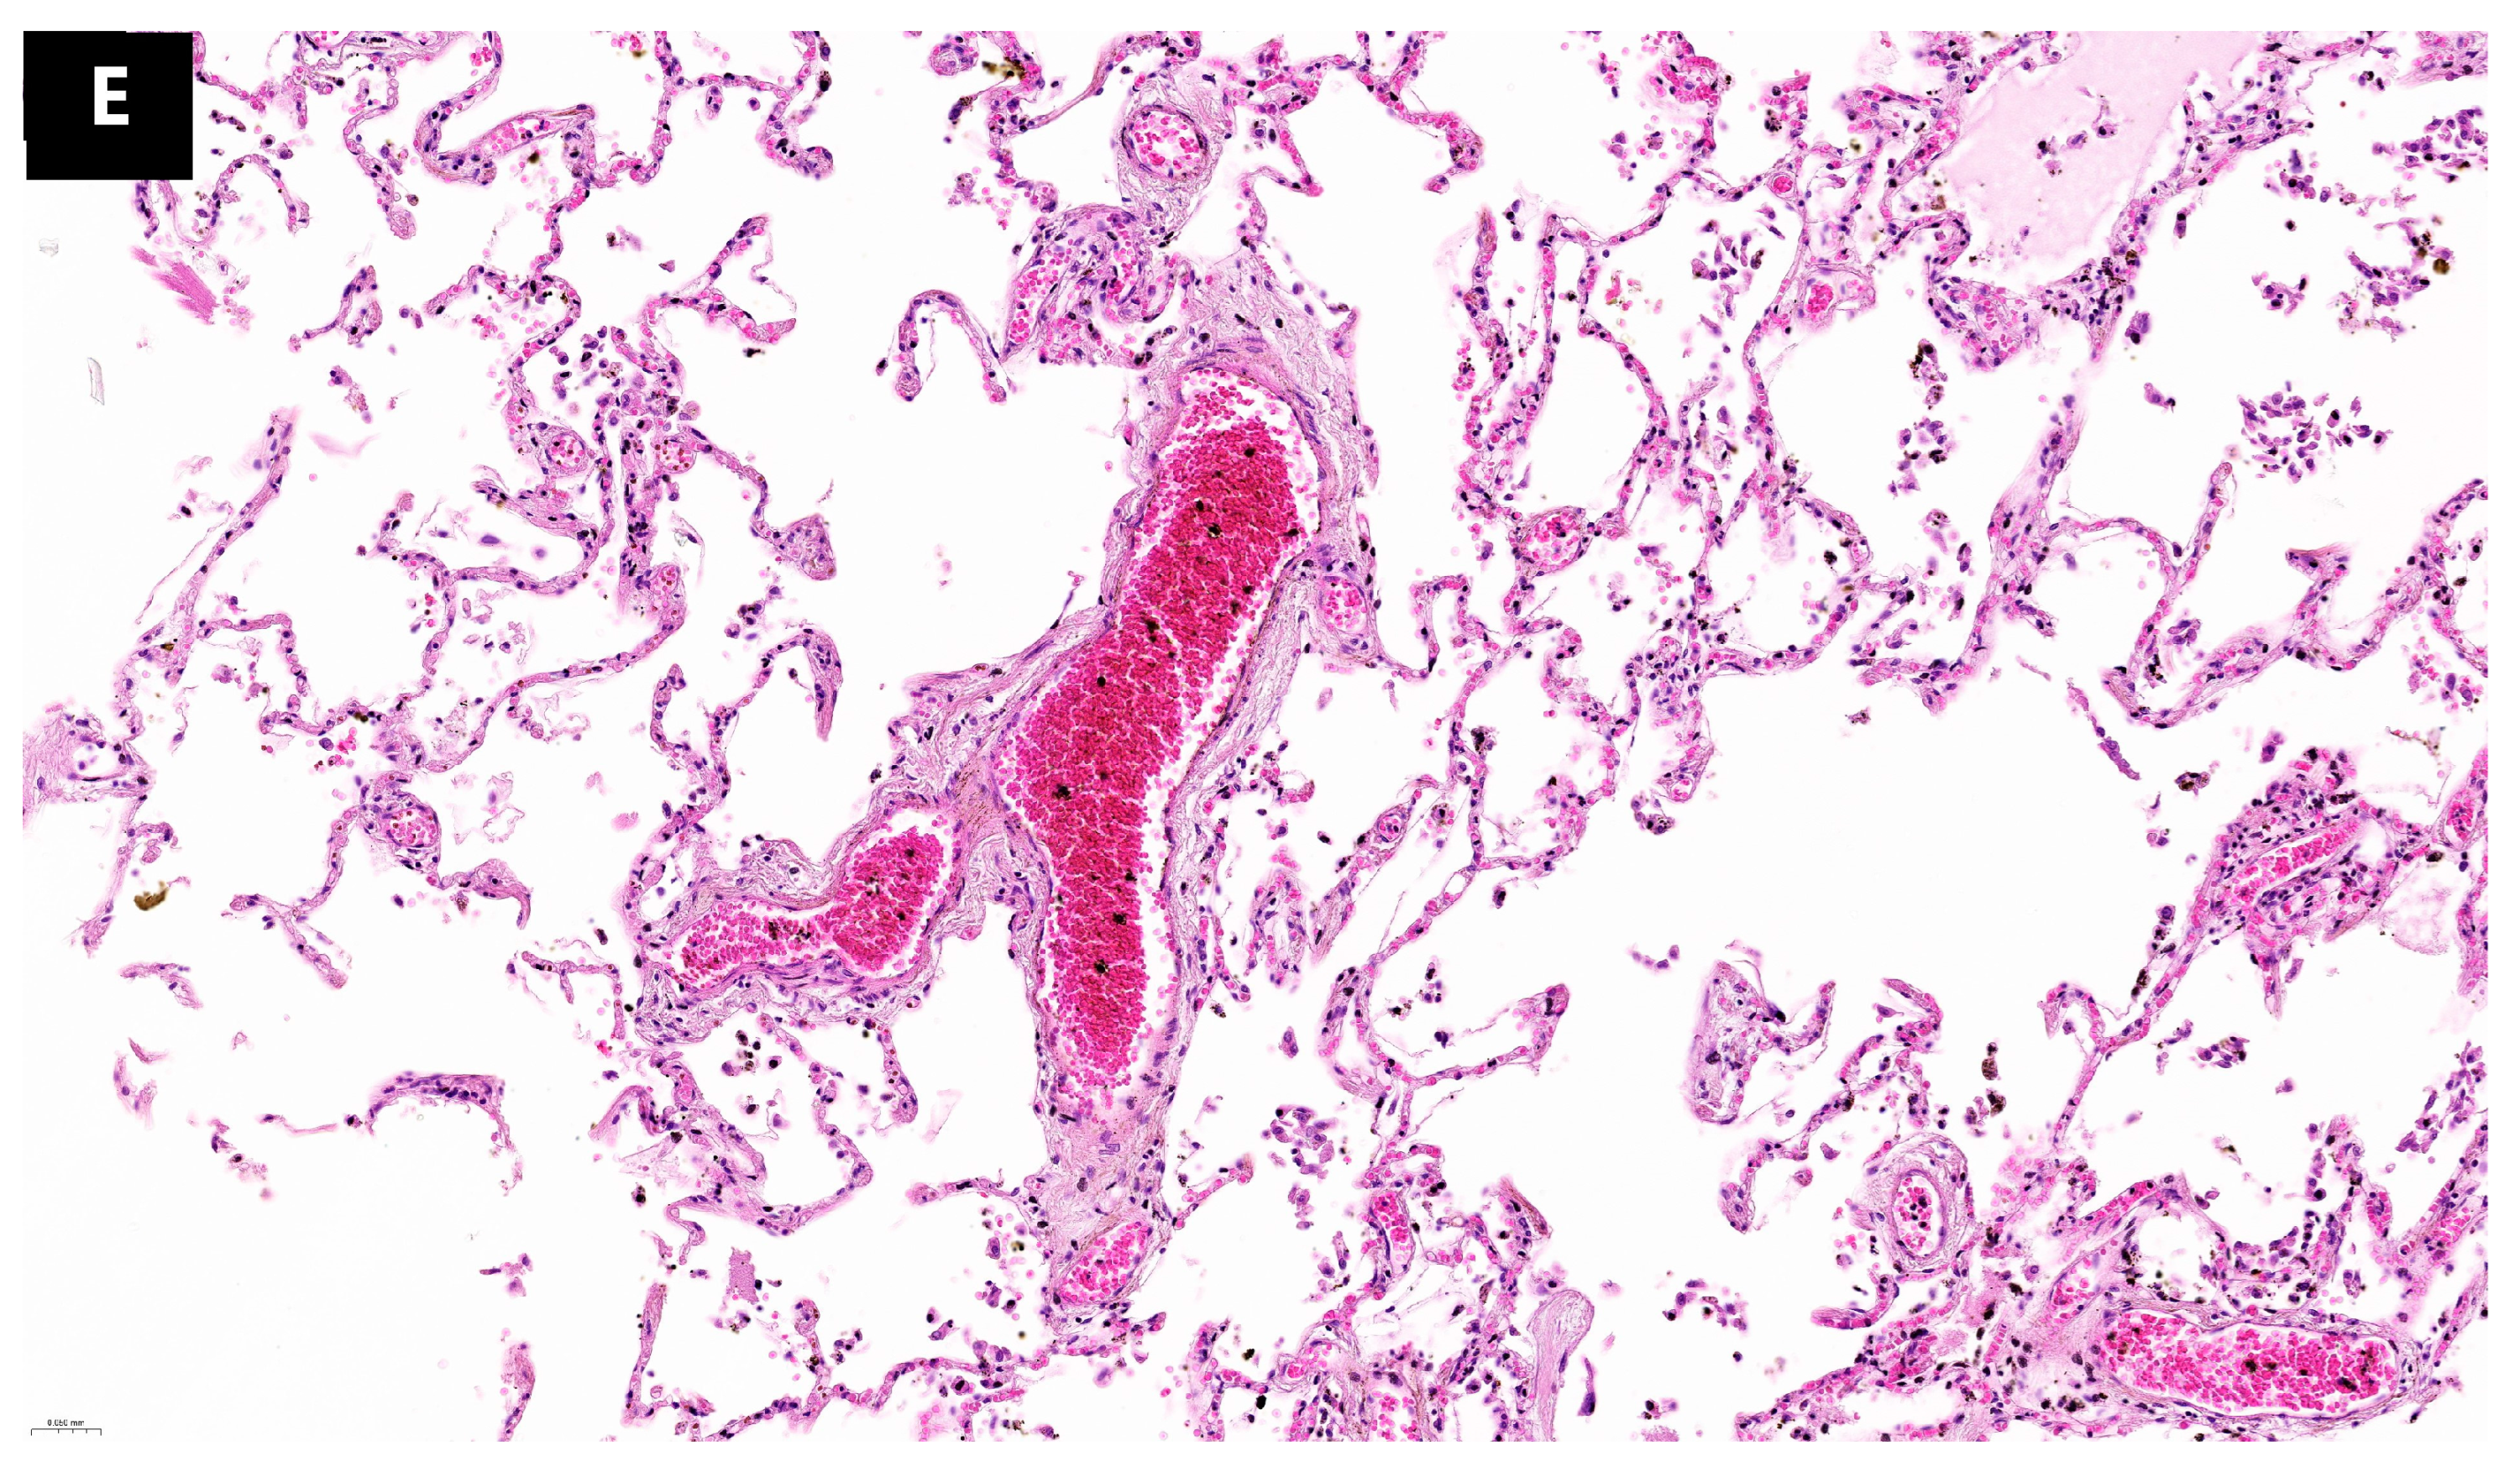

During histopathological examination, numerous microscopic lesions in the pulmonary tissue corresponding to alterations in remodeling and tissue regeneration processes were observed, likely indicative of a prolonged evolution of SARS-CoV-2 infection. These lesions, termed aberrant regenerative changes, encompassed organizing pneumonia, interstitial fibrosis, and alveolar squamous metaplasia (

Figure 3). Aberrant regenerative lesions succeeded the acute lesions of the exudative phase, including hyaline membranes, type II pneumocyte hyperplasia, alveolar hemorrhage, and inflammatory infiltrate, entering the spectrum of the proliferative organization phase within acute alveolar lesions [

18]. Thus, the study identified eight cases exhibiting at least one form of aberrant regenerative change. Among these, four cases presented organizing pneumonia, eight cases showed interstitial fibrosis, and five cases exhibited squamous metaplasia. Four cases presented all three forms described, one case presented two of the three forms, and three cases presented only one aberrant regenerative lesion. Correlating these findings with the time interval between the onset of symptoms and death, we observed that one out of three described lesions tend to emerge after a few days following infection (between 2 and 21 days) and after 23 days all three lesions described can be detected.